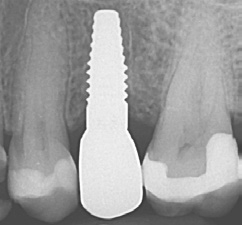

Die Implantate wurden im Anschluss mit einer ausreichenden Primärstabilität von 30 Ncm und einem suprakrestalen Anteil 0,6 mm platziert. Diese suprakrestale Positionierung wird durch einen gegebenenfalls am Profilbohrer anbringbaren Tiefenstopp (Abb. 7) vereinfacht. Für das Einbringen der Implantate steht ein neues, zur „Inter-X“-Innenverbindung formschlüssiges Eindrehinstrument (Abb. 8) zu Verfügung, wodurch eine optimale Kraftübertragung während des Inserierens des Implantats gewährleistet wird (Abb. 9). Die Einheilkappen sind deutlich abgeflacht und ermöglichen einen einfachen primären Wundverschluss (Abb. 10 und 11). Im vorliegenden Fall verlief die Wundheilung komplikationslos. Nach einer auch für Keramikimplantate heute üblichen Einheilungszeit von 3 Monaten zeigten sich die Implantate in der Röntgenkontrollaufnahme stabil osseointegriert (Abb. 12). Es fanden sich an beiden Implantat-Loci entzündungsfreie Weichgewebsverhältnisse, woraufhin mit der prothetischen Versorgung des Implantats begonnen werden konnte.

Die mit dem Abutment verklebten Restaurationen konnten nun entnommen, Zementüberschüsse (Abb. 22) sicher entfernt und die Übergänge von Krone zu Abutment poliert werden. Für die definitive Eingliederung ist der für die Abutmentschraube vorgegebene Anzugstorque von 25 Ncm einzuhalten. Nach erneutem Auffüllen der Schraubenkanäle wiederum mit Teflonband wurden die Zugangskavitäten in ebenfalls üblicher Weise mit Komposit verschlossen. Das Ergebnis sind im vorliegenden Fall 2 metall- und zementfreie, verschraubte und reversible Einzelzahnrestaurationen (Abb. 23). Bei dem routinemäßig durchgeführten Follow-up 6 Monate nach Eingliederung zeigte sich eine an beiden Implantatpositionen reizlose Weichgewebssituation (Abb. 24a und b) und in den radiologischen Kontrollaufnahmen stabile periimplantäre Knochenverhältnisse (Abb. 25a und b).